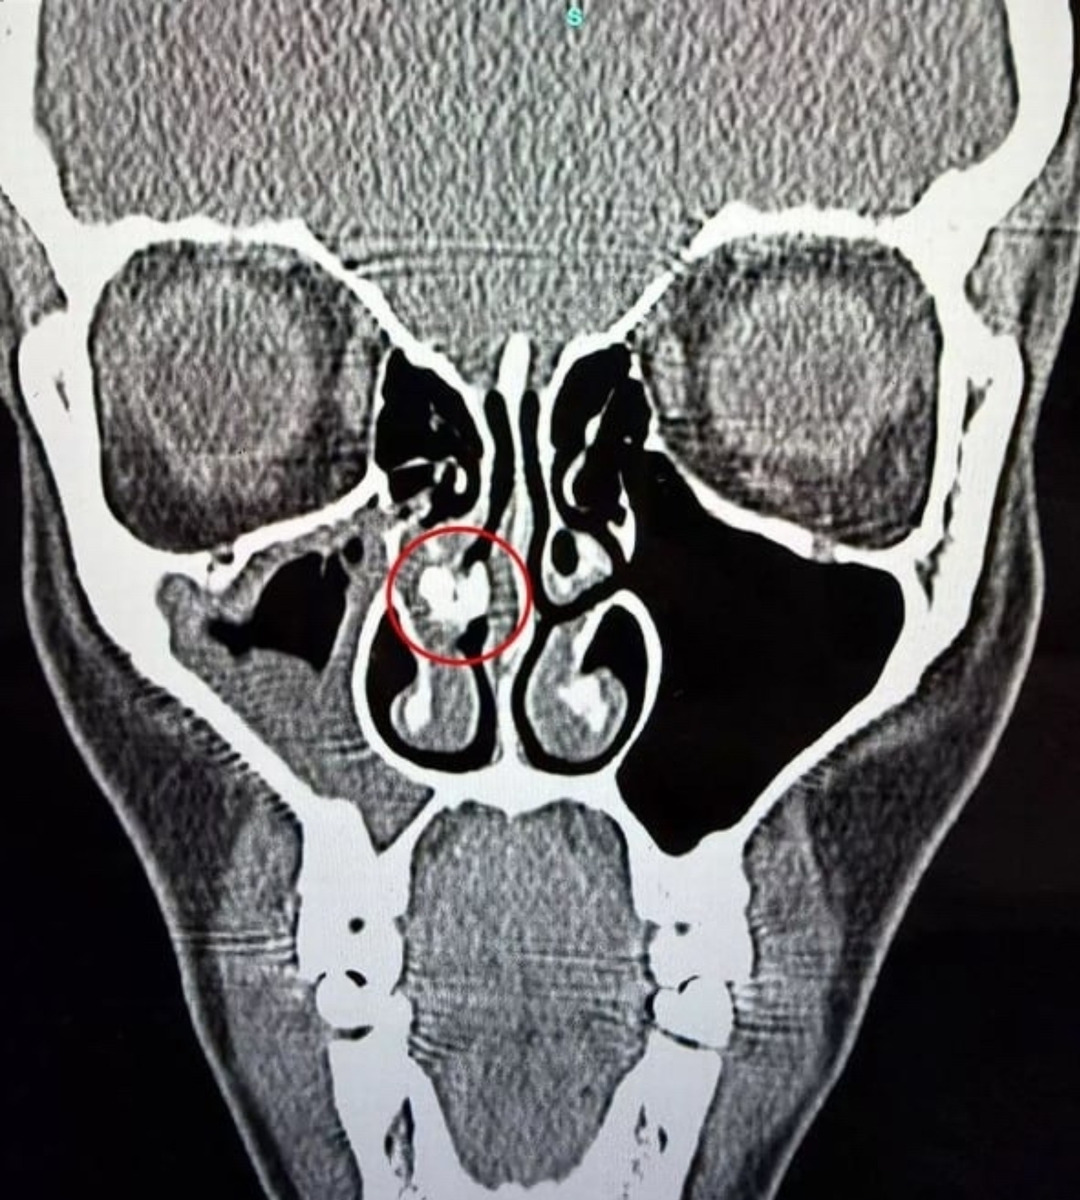

Женщина 35 лет жила с комком скотча в носу и не знала об этом

Кендела Рейбо из Великобритании испытывала трудности с дыханием столько, сколько себя помнила. Они мешали ей заниматься спортом и нормально спать. В одночасье все изменилось: проблема возникла по вине врачей в роддоме.

Они вводили ей носовую трубку, а потом просто забыли удалить пластырь. Англичанка выяснила это, когда сделала КТ после синусита. Теперь в возрасте 35 лет она наконец-то может вдохнуть полной грудью.